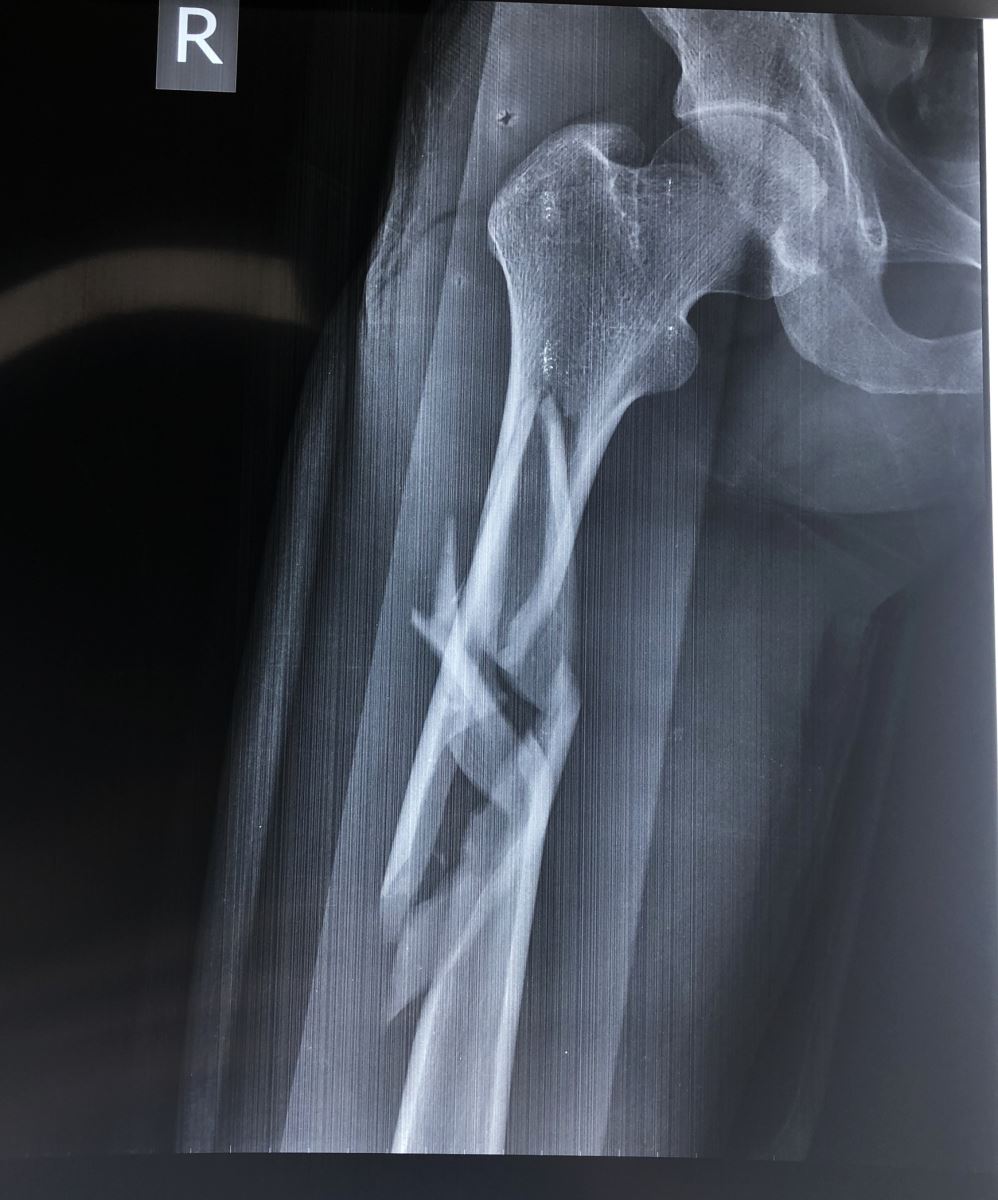

1.2. Đường gãy

Gồm có gãy ngang, gãy chéo, gãy xoắn, gãy 2 ổ hoặc gãy vụn.

- Đường gãy ngang: Thường do gập góc, dạng gãy này sau khi nắn tốt thì thường vững chắc hơn các dạng gãy khác.

- Đường gãy chéo, xoắn: Thường do gập góc kèm theo vặn xoắn cơ thể. Dạng gãy này không vững chắc sau khi nắn

1.3. Sự di lệch

Tuỳ theo vị trí gãy và có các hình thái di lệch khác nhau. Các di lệch thường gặp là gập góc, lệch sang bên, chồng lên nhau, xoay ngoài của đoạn gãy xa.

3. CHẨN ĐOÁN HÌNH ẢNH (X-QUANG)

Mặc dù chẩn đoán bằng X quang là cần thiết, nhưng cần khám kỹ lâm sàng để tránh bỏ sót thương tổn. Một số trường hợp bỏ sót trật khớp háng trong gãy thân xương đùi vì chỉ chụp giới hạn ổ gãy. Do vậy để có một phim X quang tốt cần chú ý:

- Chụp lấy được 2 khớp của đầu xương gãy ít nhất hai bình diện thẳng và nghiêng.

Áp dụng cho các trường hợp gãy thân xương đùi, tốt nhất đoạn 2/4 giữa, áp dụng trong tất cả các trường hợp gãy ngang, chéo, nhiều mảnh, gãy 2 ổ. Đóng đinh nội tủy được xem là phương pháp tốt nhất hiện nay. Nhờ màn tăng sáng, người ta đóng đinh không mở ổ gãy và có khoan rộng ống tủy. Để chống xoay của đoạn gãy xa người ta tăng cường chốt ngang qua xương. Trong trường hợp đường gãy thấp ở đoạn 1/3 giữa và dưới, có thể tiến hành đóng đinh nội tủy có chốt ngang ngược dòng từ đầu dưới xương đùi.